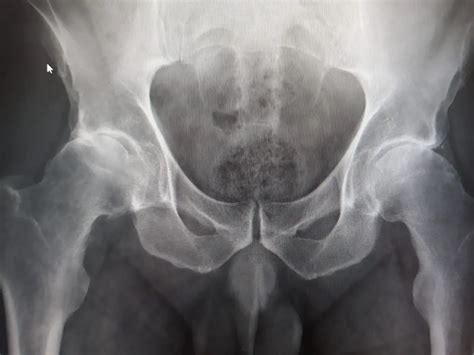

Diagnosing artrosis de cadera typically involves a combination of medical history, physical examination, and diagnostic tests. The diagnostic process may include:

• Imaging Tests: X-rays, MRI, or CT scans to visualize the hip joint and assess the extent of cartilage damage.